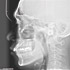

Nacholgend ein paar phänomenale Bilder & Werte,

die nicht nur einem Fachmann die Sprache verschlagen:

Aufnahmeparameter: Ceph LA; 82 kV; 10 mA; 8.0 s; 0.8 mm CU + 6.0 mm AL

gemessene Dosis: 2.99 µGy